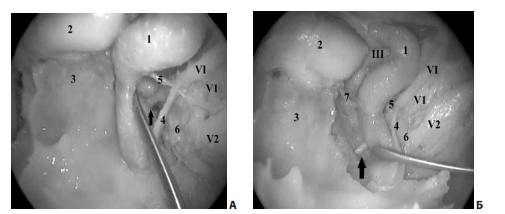

В полости кавернозного синуса от ВСА отходят несколько артериальных стволов, наиболее постоянным из которых являются менинго-гипофизарный и нижне-боковой (рис. 5).

Рис. 5. Латероселлярное пространство (анатомический препарат): А — вид с помощью 0º эндоскопа; Б — вид с помощью 45º эндоскопа; 1 — кавернозный сегмент ВСА; 2 — гипофиз; 3 — скат; 4 — симпатическое нервное сплетение ВСА; 5 — нижне-боковой артериальный ствол; Б — ганглий тройничного нерва; 7 — менинго-гипофизарный артериальный ствол; III — глазодвигательный нерв; VI — отводящий нерв; V1 — глазной нерв (первая ветвь тройничного нерва); V2 — верхнечелюстной нерв (вторая ветвь тройничного нерва); стрелкой указано место входа отводящего нерва в полость кавернозного синуса из канала Дорелло.

Отводящий нерв входит в кавернозный синус из канала Дорелло и обычно располагается латеральнее ВСА на уровне верхнего края глазного нерва. Стоит отметить, что сосудистое сплетение ВСА, поднимаясь вдоль паракливального отдела ВСА, доходит до отводящего нерва, что может являться ориентиром для обнаружения VI ч.м.н. при осуществлении транссфеноидального доступа к кавернозному синусу через его передне-нижние отделы (рис. 5).